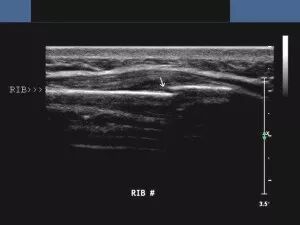

正常肱骨内上髁超声影像

肌骨超声,具备实时动态成像、操作简便高效、无辐射、双侧对比观察、互动性好、可实施引导介入治疗等优势,已被越来越多地应用于肌肉骨骼系统及软组织疾病的诊断治疗中。超声波不能穿透骨骼,仅能显示探头侧的骨皮质,骨皮质在正常骨骼声像图上表现为连续、规则的线状明亮强回声,因此可以利用这一特征对骨折进行判断。

肋骨骨折

肌骨超声对于微小骨折的诊断,有时甚至超过了传统的X线、CT、MRI等检查。它可以清晰显示软骨骨折线,对软骨骨折的检出率要明显高于x线,能发现x线检查易漏诊的肋骨、甲状软骨骨折等。超声检查还能准确诊断与韧带、肌腱相连处的长骨骨皮质发生的撕脱性骨折,其诊断敏感性达90.2%、 特异性达96.1%。